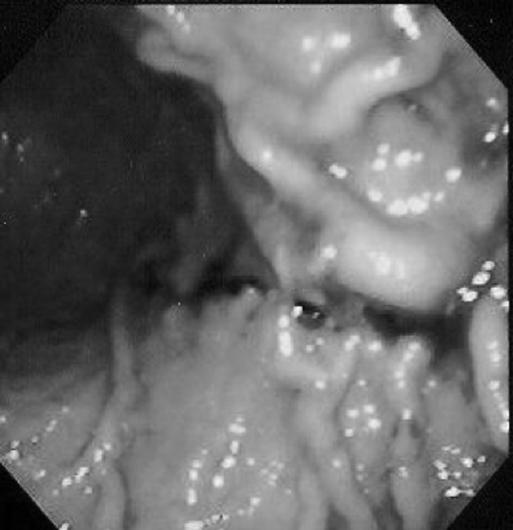

A 70-year-old female with a history of bleeding from Osler-Weber-Rendu disease presented to the emergency department complaining of hematemesis. Her vital signs were unstable, and she was immediately resuscitated with intravenous fluids and transfusions. A combined laparoscopic and intraoperative endoscopic approach to a partial gastric resection was planned. Intraoperatively, a single lesion was identified along the posterior aspect of the greater curvature of the stomach by using endoscopy. The blood supply was taken down with a Ligasure and gastric resection with a 60-mm Echelon stapler.

一名有遗传性出血性毛细血管扩张症出血史的70岁女性因呕血就诊于急诊科。她的生命体征不稳定,立即通过静脉输液和输血进行复苏。计划采用腹腔镜和术中内镜联合进行部分胃切除术。术中,通过内镜在胃大弯后侧发现一个单一病变。使用结扎速血管闭合系统切断血供,并用60毫米的Echelon吻合器进行胃切除。